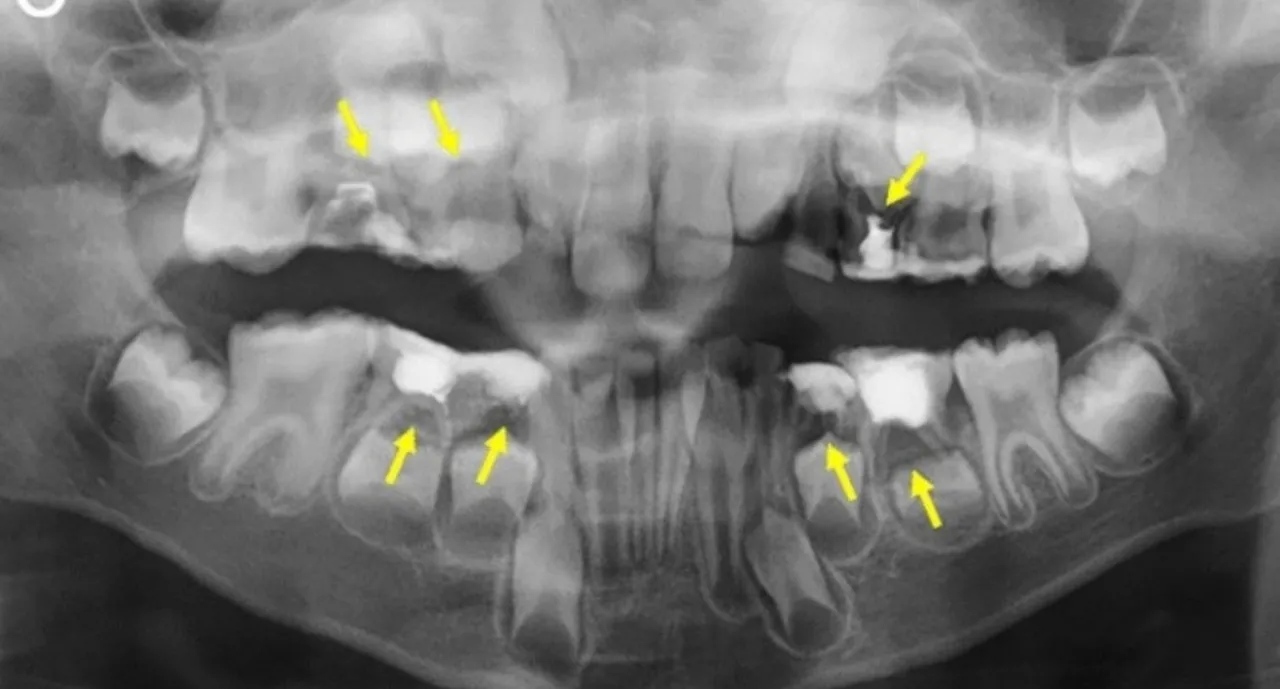

Diagnostyka od wywiadu po zdjęcie RTG

Pierwszym krokiem jest zawsze szczegółowy wywiad, podczas którego zapytam o Twoje objawy, ich nasilenie, czas trwania oraz ewentualne inne dolegliwości. Następnie przeprowadzę badanie fizykalne jamy ustnej, oceniając stan zębów, dziąseł i tkanek miękkich. Kluczowym elementem diagnostyki jest wykonanie zdjęcia RTG (np. pantomograficznego lub punktowego). Pozwala ono dokładnie zlokalizować źródło problemu czy to ropień okołowierzchołkowy, problem z ósemką, czy zaawansowana próchnica.